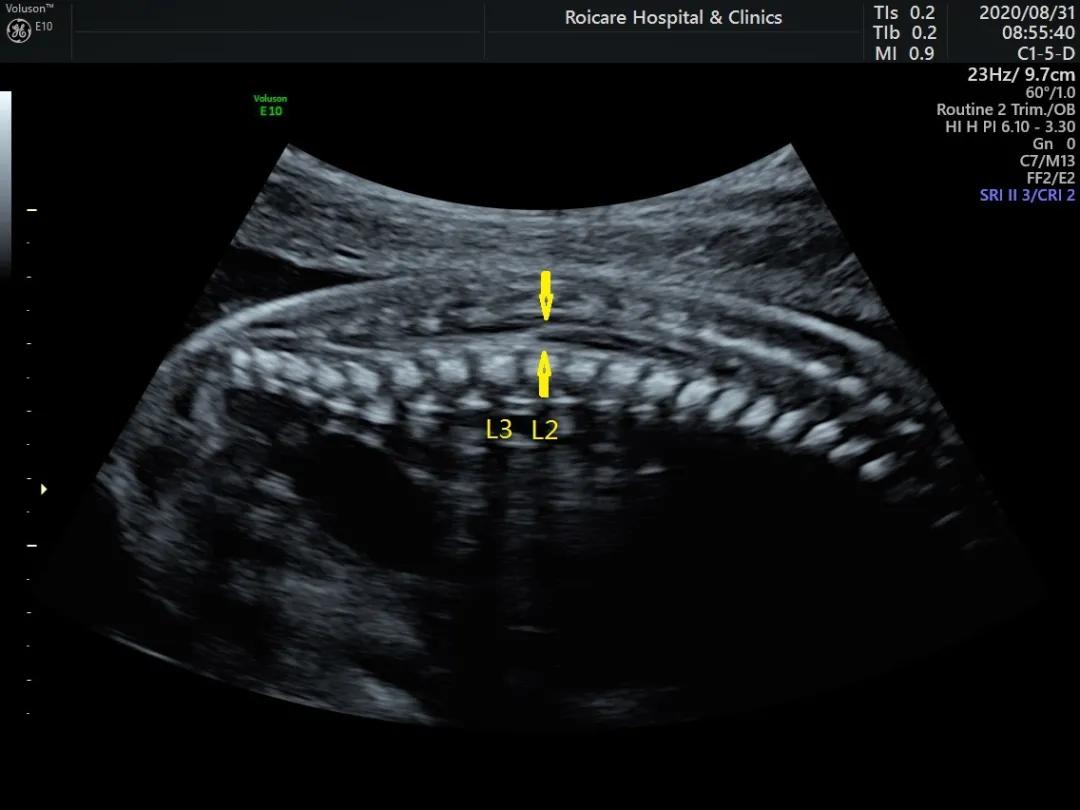

正常位置的脊髓圆锥

出生时脊髓圆锥位于第2腰椎(L2)至第3腰椎(L3)水平,出生后3个月位于L1~L2水平,与成人相同。脊髓下端因各种先天或后天原因受制于椎管的末端不能正常上升,使其位置低于正常,由此而导致的一系列临床神经功能障碍和畸形的综合征即称为脊髓拴系综合征。

正常孕20周以上的胎儿脊髓圆锥的位置达到L3水平以上,如果孕20周以上胎儿脊髓圆锥位置在L4以下,要警惕脊柱裂可能以及是否合并其他异常。中孕期产前超声检查可以发现严重的开放脊柱裂。闭合性脊柱裂表现多样、脊柱裂口小、影像学表现不典型,因此产前超声诊断困难。

脊髓圆锥低位